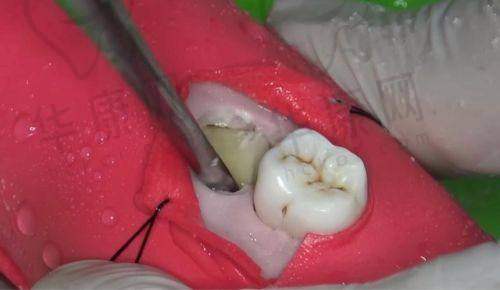

南京江宁牙管家口腔拥有一支经验多、技术不错的医生团队。在阻生智齿拔除方面,医生们具备专精的知识和丰富的临床经验,能够根据患者的具体情况制定个性化的治疗方案。例如,主推的种植医生邱涛,虽然他在种植牙领域表现出色,但整个医生团队在拔牙等口腔治疗方面同样有着深厚的造诣。医生们在操作过程中手法娴熟,能够较大程度地减少患者的痛苦,确保手术的顺利进行。

江宁牙管家口腔此次推出的阻生智齿拔除641元起的价格,是根据智齿的生长情况和拔除难度来定价的。一般来说,智齿位置比较正,拔除难度较低的,费用可能在500 - 1000元之间;而如果智齿是阻生齿或者位置较深,需要切开牙龈或磨除部分牙槽骨,费用会高一些,大概在1000 - 3000元不等。这种灵活的定价方式,能够让患者根据自身情况选择合适的治疗方案,既确保了治疗成效,又能在一定程度上减轻患者的经济负担。